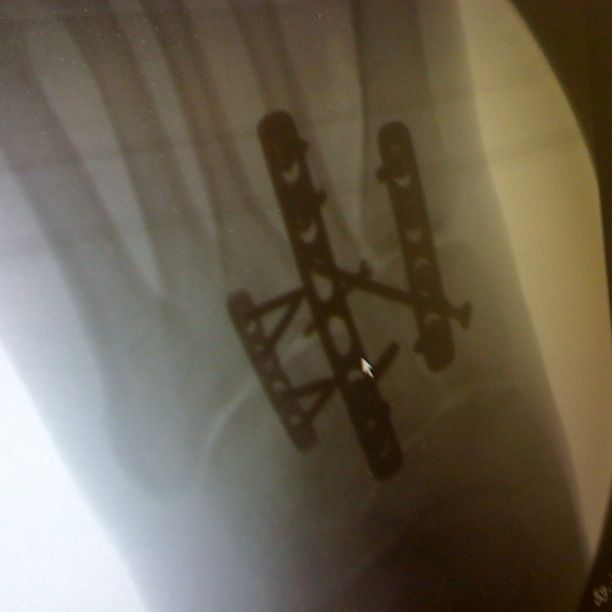

After X-rays and prods I was told I had sustained a Lisfranc injury. Lisfrancs was a surgeon and gynecologist in Napoleans army. I have no idea why Napolean needed a gynecologist, but for me it basically meant I had torn all the ligaments attached to my metatarsals, plus dislocated and fractured the bones in the mid-foot.